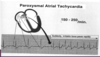

Paroxysmal atrial tachycardia has a sudden onset and what is the HR?

Rate = 150-250/min

Interpret this EKG

Atrial Tachycardia with 2:1 AV block

Interpret this EKG

Atrial Tachycardia w/ 2:1 AV block